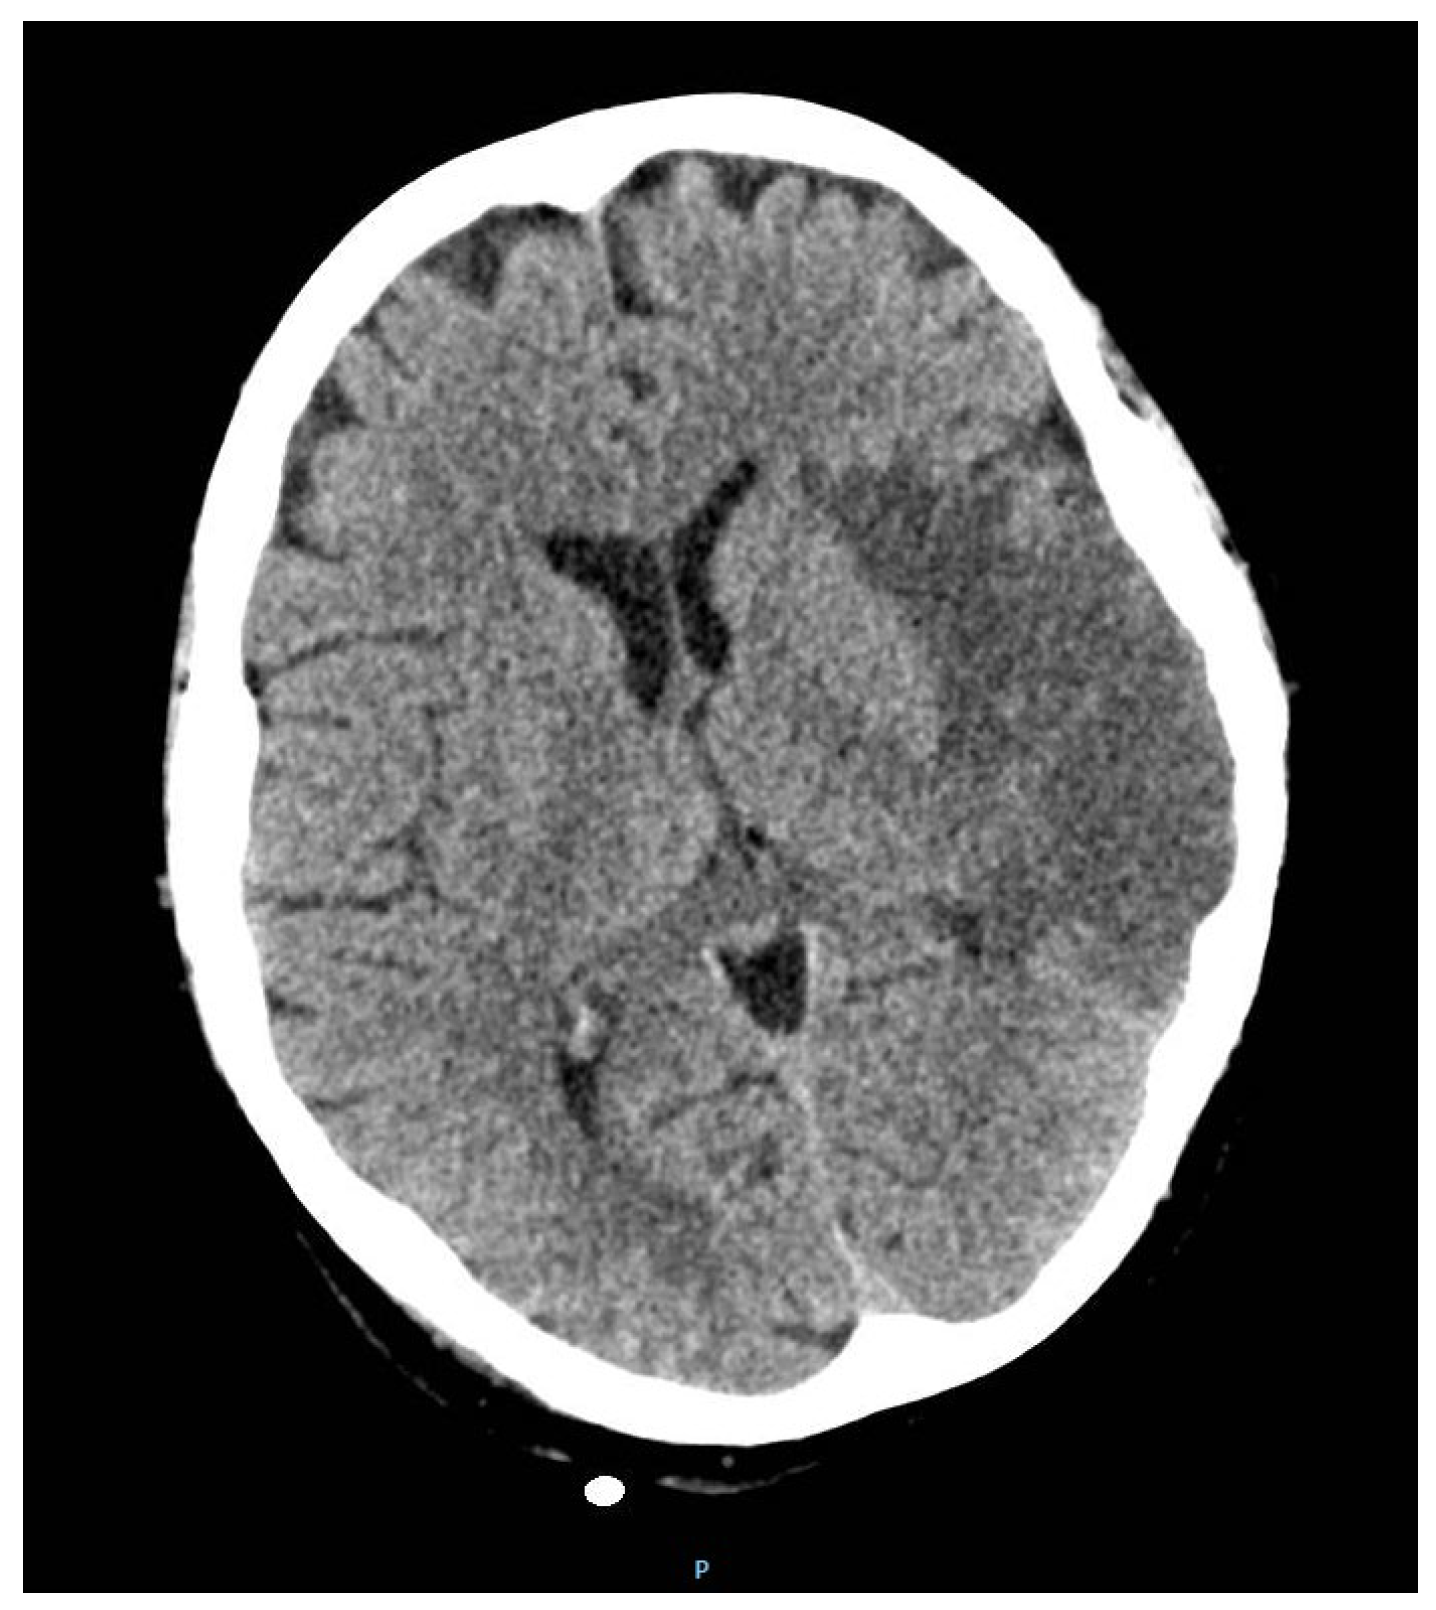

Rare Case of Grade 3 Undifferentiated Pleomorphic Sarcoma in Left Atrium, Mitral Valve, and Papillary Muscle

2. Case Report